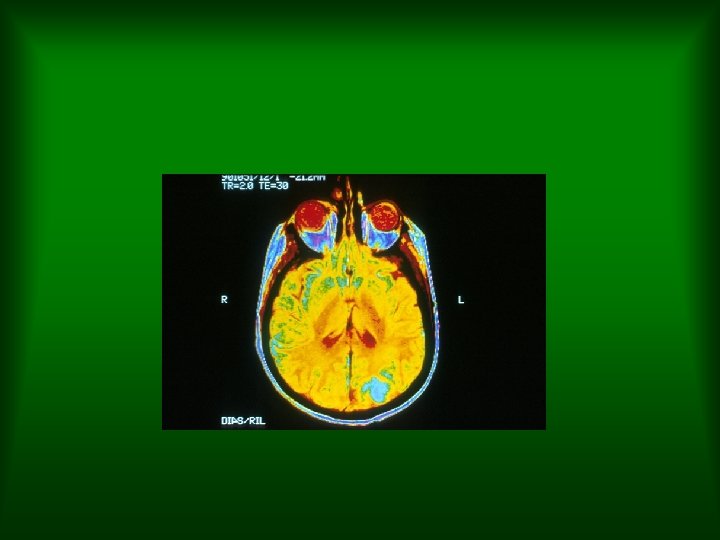

1960 Chromosome abnormality associated with leukemias. 1961 M. Nirenberg and others prove triplet code is how the information to make proteins is stored in DNA. Dr. Emil Freireich working with a blood cell separator centrifuge at M. D. 1962 Royal College of Anderson Hospital. Physicians issues report on smoking and health.